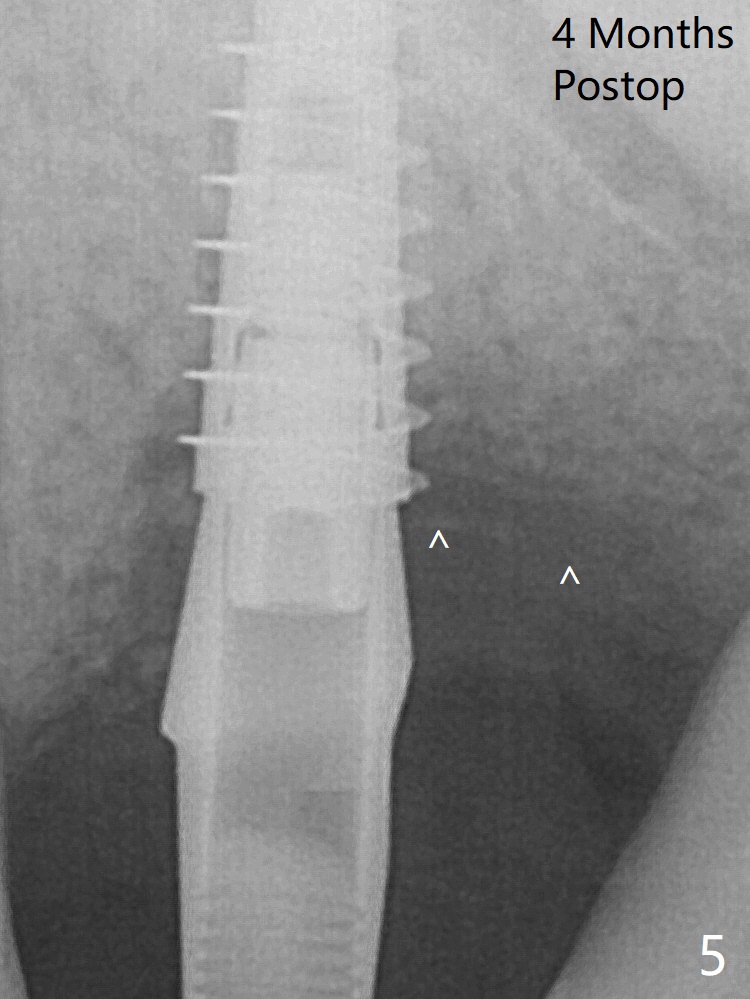

术后4个月骨粉好像覆盖远中曾经暴露螺纹(图五:^)。植体仿佛保留骨粉,促进新骨形成。

暴露螺纹     Last     Next